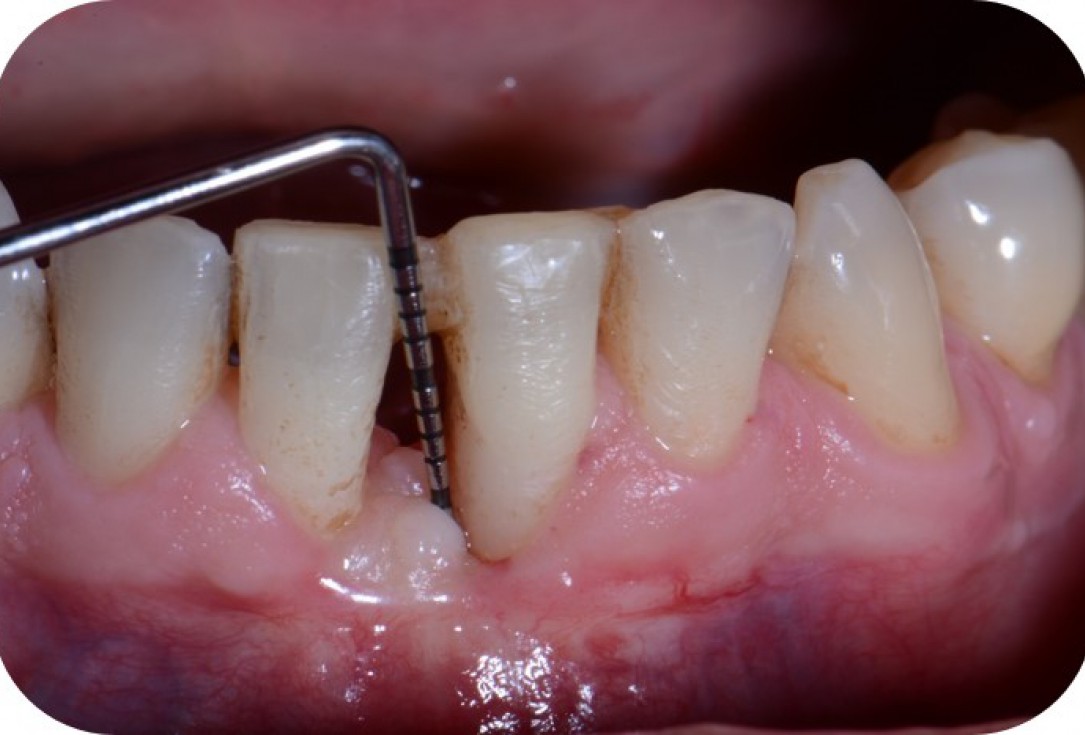

01/12 - Pre-operative clinical situation.Two-wall intrabony defect treated using cerabone® and Straumann® Emdogain® - Dr. D. Rakasevic & Prof. Dr. S. Jankovic